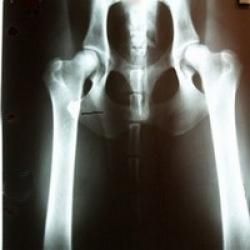

Hunden bedøves let, lægges på ryggen med benene strakt helt ud, og der tages et røntgenbillede af dens hofteled i denne position.

Hunden bedøves let, og der tages i alt 3 billeder af dens hofteled:

Et standard HD-billede som ovenfor beskrevet, et kompressions-billede hvor hofteleddet trykkes sammen, samt et distraktions-billede, hvor hofteleddet udsættes for et let press.